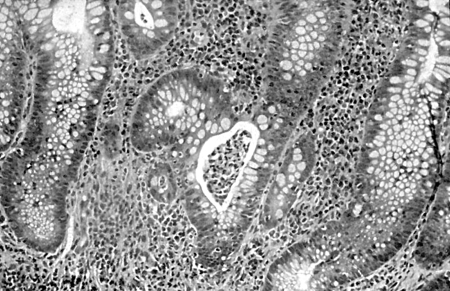

Colitis ulcerosa

Muestra de la biopsia del colon que muestra inflamación grave de la mucosa, formación de abscesos en las criptas, atrofia glandular leve y distorsión, lo que sugiere una fase activa de colitis ulcerosa; tinción con hematoxilina y eosina, ampliación ×400.

De Iannone F, Scioscia C, Musio A, et al Leucocytoclastic vasculitis as onset symptom of ulcerative colitis Ann Rheum Dis 2003;62(8):785-6; utilizado con autorización